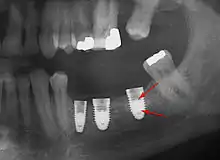

Bone loss (peri-implantitis) on implants over 7 years in a heavy smoker

Fixture show

Recession of the gingiva leads to exposure of the metal abutment under a dental crown.

Fracture of abutment screws (arrow) in 3 implants required removal of the remainder of the screw and replacement.

Cement peri-implantitis

Dental cement under the gingiva causes peri-implantitis and implant failure.